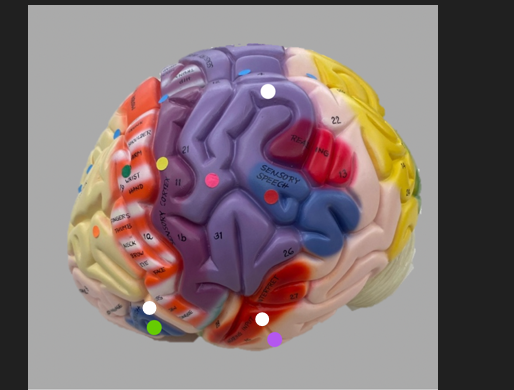

orange dot

frontal lobe

blue dot

longitudinal fissure

dark green dot

precentral gyrus

pink dot

postcentral gyrus

yellow dot

central sulcus

white dot

parietal lobe

light green dot

Broca’s Area

red dot

Wernicke’s Area

orange dot

occipital lobe

blue dot

parieto-occipital sulcus